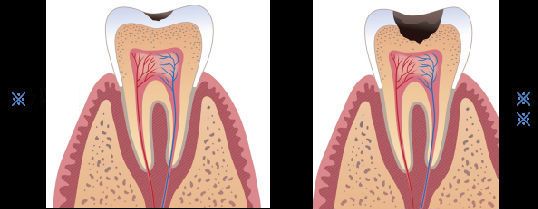

浅龋,早期中轻度龋齿即小面积蛀牙——补牙

俗话说:“千里之堤毁于蚁穴。”发现小的漏洞就应该及时补救,其实牙齿也一样。有了龋齿(蛀牙虫牙)或缺损就应尽早补牙,因为龋洞在经过修补后可以阻止龋病病变的发展,及早恢复牙齿的形态和功能,保持牙列的完整。